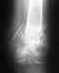

Был перелом лючевой кости правой руки со смешение.

Сделали операцию поставили пластинку, наложили шину. Сняли через месяц шину сделали рентген. Все ыло в порядке. Пластину будут снимать через 7 месяцев. Но главное в том что через неделю после снятия шины на шве появилась опухоль еще через неделю она прорвала. Врачи сказали что возможно нитки внутреннего шва не рассосались. Но они так и невышли еще через две недели появился второй нарыв он тоже прорвал. Врачи чистили сказали что они межде собой связаны вливали в одип нарыв вылевалось со второго. Так было недели. Начало затягиваться. Все заросло помазали зеленкой. Но вот прошло полторы недели и опять в старых же местах поизошли нарывы лечение проводят тоже самое. Пластину снимать будут только в феврале.Вопрос причину гнеения объяснить немогут. Боюсь неделю почистят зарастет а потом все заново. Когда шевелю кистью чувству пластину, нормально ли это.

Вы описываете клиническую картину глубокой инфекции после операции. Ваши ощущения ("чувству пластину, нормально ли это") могут быть самыми разнообразными. Для устранения проблемы нужны достаточно серьёзные действия - выявление очага инфекции, его хирургическая обработка. Если не вовлечена зона перелома - это легче.